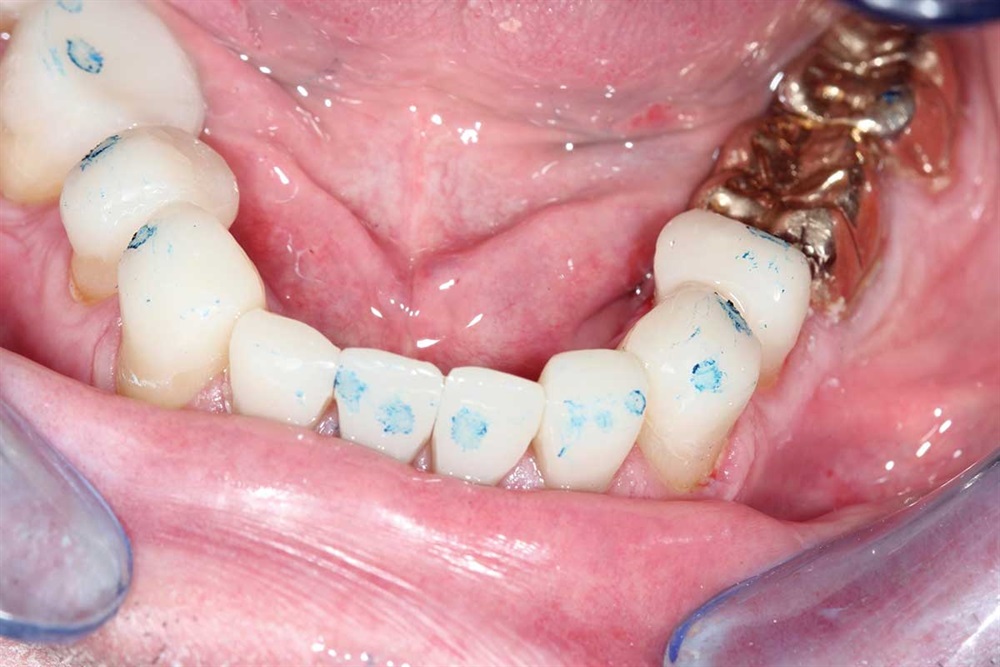

Fig. 7: Z250 A2 composite, AllBond 2 and Premier Dental Cure-Thru matrix bands were used.

Show Your Work

Fig. 8: First tooth done, but not finished. I built up the incisors about 5mm.